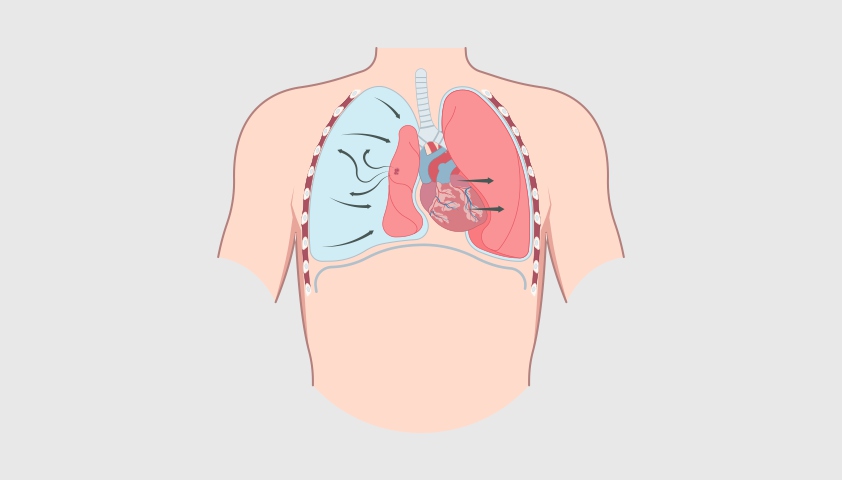

Напряжённый пневмоторакс — самый опасный вид заболевания, когда воздух попадает в грудную полость и нарушает работу не только лёгких, но и сердца, создавая избыточное давление. В результате лёгкое сжимается, сердце и сосуды смещаются, что может привести к жизнеугрожающему состоянию. Без срочной медицинской помощи это может привести к остановке дыхания. Распознать состояние можно по резкой нехватке воздуха, посинению кожи, набуханию вен на шее и резкому падению давления.

Наиболее опасен напряжённый пневмоторакс — состояние, возможное при пневмотораксе любого типа, при котором воздух непрерывно поступает и накапливается под давлением, деформируя лёгкое и смещая сердце.

Напряжённый пневмоторакс — одно из самых грозных последствий. При этом состоянии воздух активно поступает в плевральную полость по принципу одностороннего клапана и не может выйти из неё. Воздуха скапливается так много, что лёгкое сжимается, а сердце и сосуды смещаются в сторону. Человек начинает задыхаться — падает давление, учащается пульс, синеет кожа. Без срочной помощи возможна потеря сознания и даже остановка сердца.